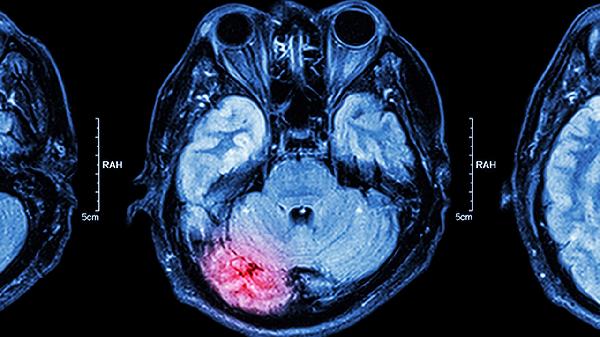

脑软化灶会带来哪些影响

脑软化灶可能引发一系列神经功能问题,比如记忆力下降、行动不便、癫痫发作、情绪波动以及感觉异常等。这种病变通常是由于脑部供血不足导致的组织坏死,常见于脑梗死、脑外伤或脑炎等情况。

脑软化灶患者应保持清淡饮食,减少盐分和脂肪的摄入,同时将血压和血糖控制在正常范围内。每周安排3到5次有氧运动,如散步或游泳,强度以不引起不适为宜。避免吸烟饮酒等不良习惯,防止进一步损伤脑血管。定期复查头颅MRI,观察病灶的变化情况。一旦出现新发症状或原有症状加重,应及时前往神经科就诊。